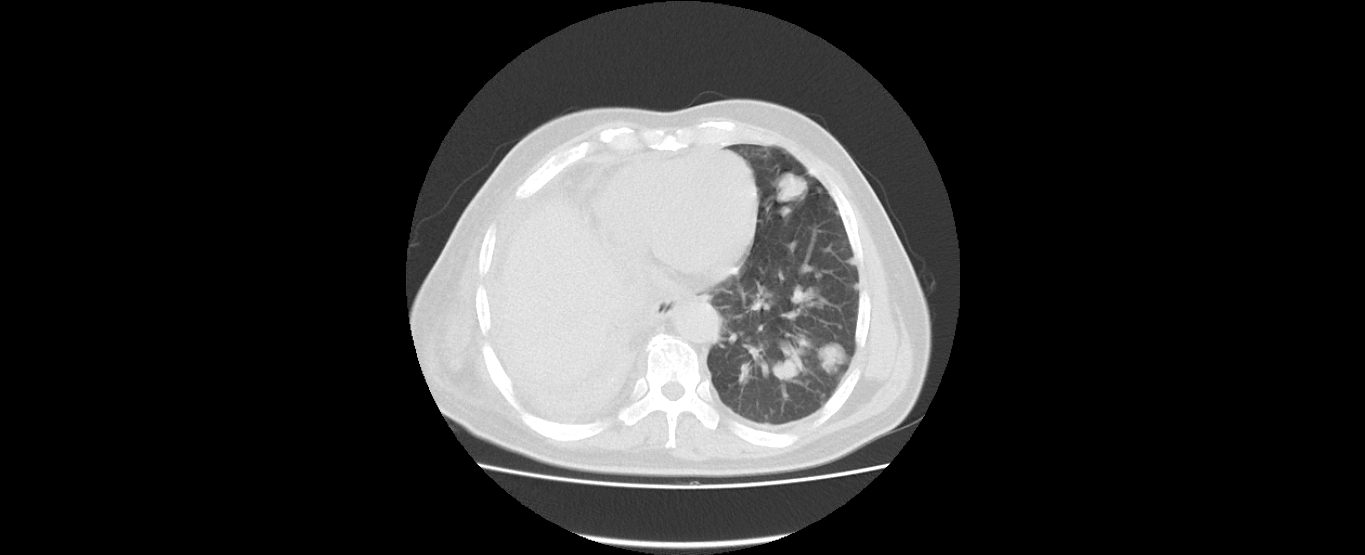

患者刘某某,男,60岁,因“右下肺中央型肺癌”2008年6月在外院行“右下肺癌根治术+右上肺部分切除术”,术后行化疗和放疗。2011年4月复查CT提示肿瘤复发,行化疗及靶向药物治疗,肿瘤控制;2016年8月新发肺转移,再次行化疗及靶向治疗,辅助中医药治疗,2017年2月复查,病情平稳。目前患者生活质量较好,没有不适症状,按时返院复查。

2016年8月

2017年2月